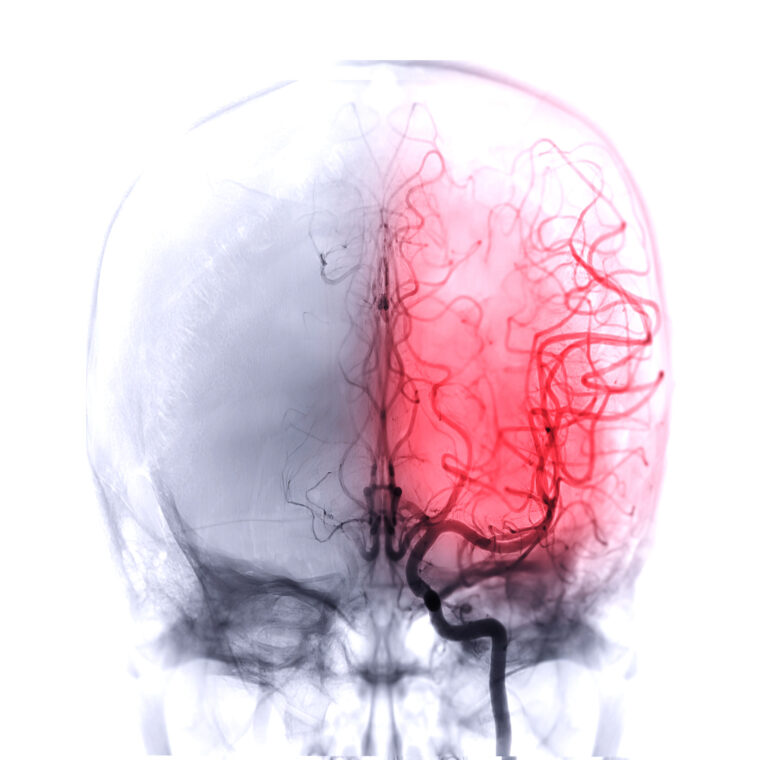

A brain scan where the left side of the brain is highlighted in red to indicate brain damage from a stroke misdiagnosis.